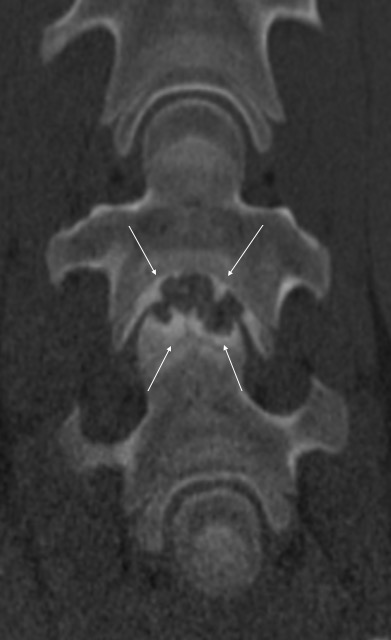

Pokud neurologické vyšetření potvrdí ataxii (stupeň 1–5), je potřeba stanovit její přesnou příčinu. Nejčastěji se jedná o zúžení páteřního kanálu v oblasti krčních obratlů, kde pak dochází k útlaku míchy – Wobblerovu syndromu. Existují ale i další příčiny ataxie, které je potřeba vzít na vědomí, například vrozené abnormality krčních obratlů (vertebrální malformace), úrazy krční páteře, nádory, virové infekce (EHV), bakteriální infekce (abscesy, záněty meziobratlových plotének a kostí) (obr. 2a, b, c), parazitární infekce nebo některé toxiny.

Obrázek 2a, b: Hříbě s ataxií a horečkou způsobenou zánětem kostí obratlů C6–C7. Na CT je jasně patrné výrazné poškození kostí v důsledku infekce (bílé šipky). Na obrázku 2b je stejný případ z jiného pohledu